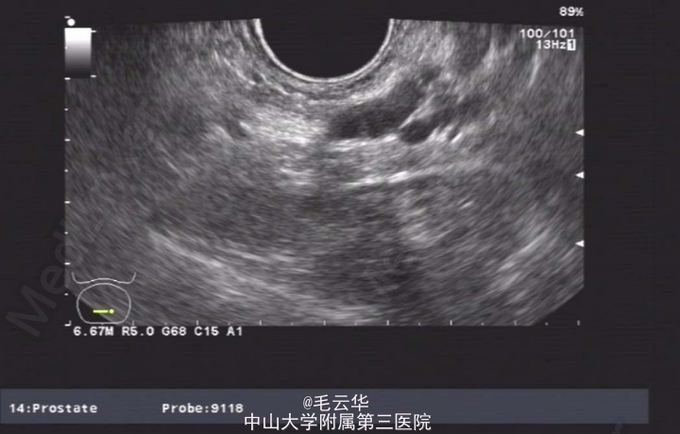

双肾区无红肿、隆起,无叩痛,双侧肋脊点、肋腰点无压痛。腹平软,双侧上中输尿管点无压痛,膀胱区无压痛。双侧腹股沟区未触及肿物,尿道外口未见异常,阴囊无水肿,双睾丸可触及,肛周皮肤无红肿。盆腔MR提示:双侧精囊腺体积缩小(未见片)。彩超提示:右侧输精管、精囊缺如可能;双侧睾丸偏大,附睾小管扩张;前列腺囊肿。精液常规提示精液量少,离心后无精子。

入院诊断:无精症查因。 入院完善术前相关检查,射精管切开+输精管探查术。麻醉成功后,取截石位,常规消毒铺巾,连接好4.5/6.5F输尿管硬镜和监视系统。经尿道进镜入膀胱,见双侧输尿管开口裂隙状,膀胱内未见异常。尿道未见明显异常,精阜稍隆起。镜下未找到双侧射精管开口,硬膜外导管引导进镜入前列腺小囊,见囊腔狭小,囊壁炎性增厚,囊内未见射精管开口,考虑射精管口梗阻,遂换用电切镜,切除部分精阜,切开双侧射精管口,再用硬膜外导管引导输尿管硬镜入射精管,进入困难,结合病史及影像学检查,提示射精管发育不良并梗阻。作双侧阴囊切口,逐层切开,游离出睾丸和精索,探查双侧输精管,见左侧输精管呈纤维条索状,未见管腔结构,右侧未见输精管,考虑为先天缺如,遂行双侧睾丸活检,术野予以止血,逐层缝合切口,术毕。手术过程顺利,麻醉效果满意,术中无出血,术后安返病房。